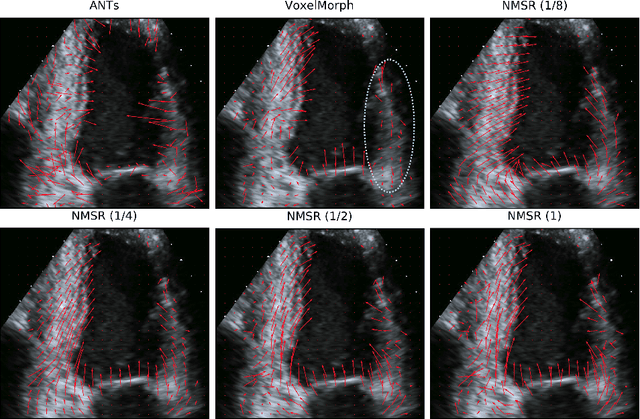

Abstract:Echocardiography has become routinely used in the diagnosis of cardiomyopathy and abnormal cardiac blood flow. However, manually measuring myocardial motion and cardiac blood flow from echocardiogram is time-consuming and error-prone. Computer algorithms that can automatically track and quantify myocardial motion and cardiac blood flow are highly sought after, but have not been very successful due to noise and high variability of echocardiography. In this work, we propose a neural multi-scale self-supervised registration (NMSR) method for automated myocardial and cardiac blood flow dense tracking. NMSR incorporates two novel components: 1) utilizing a deep neural net to parameterize the velocity field between two image frames, and 2) optimizing the parameters of the neural net in a sequential multi-scale fashion to account for large variations within the velocity field. Experiments demonstrate that NMSR yields significantly better registration accuracy than state-of-the-art methods, such as advanced normalization tools (ANTs) and VoxelMorph, for both myocardial and cardiac blood flow dense tracking. Our approach promises to provide a fully automated method for fast and accurate analyses of echocardiograms.